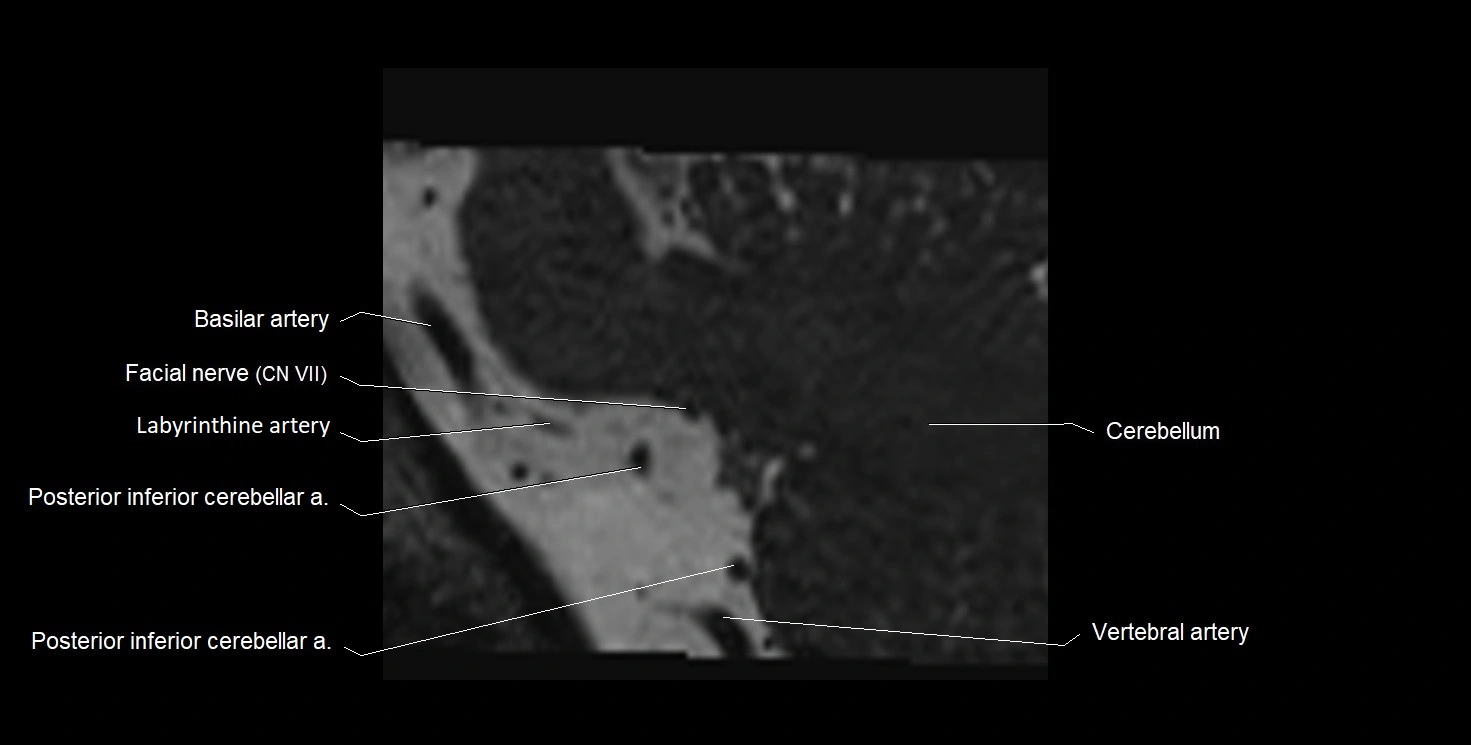

MRI images

image